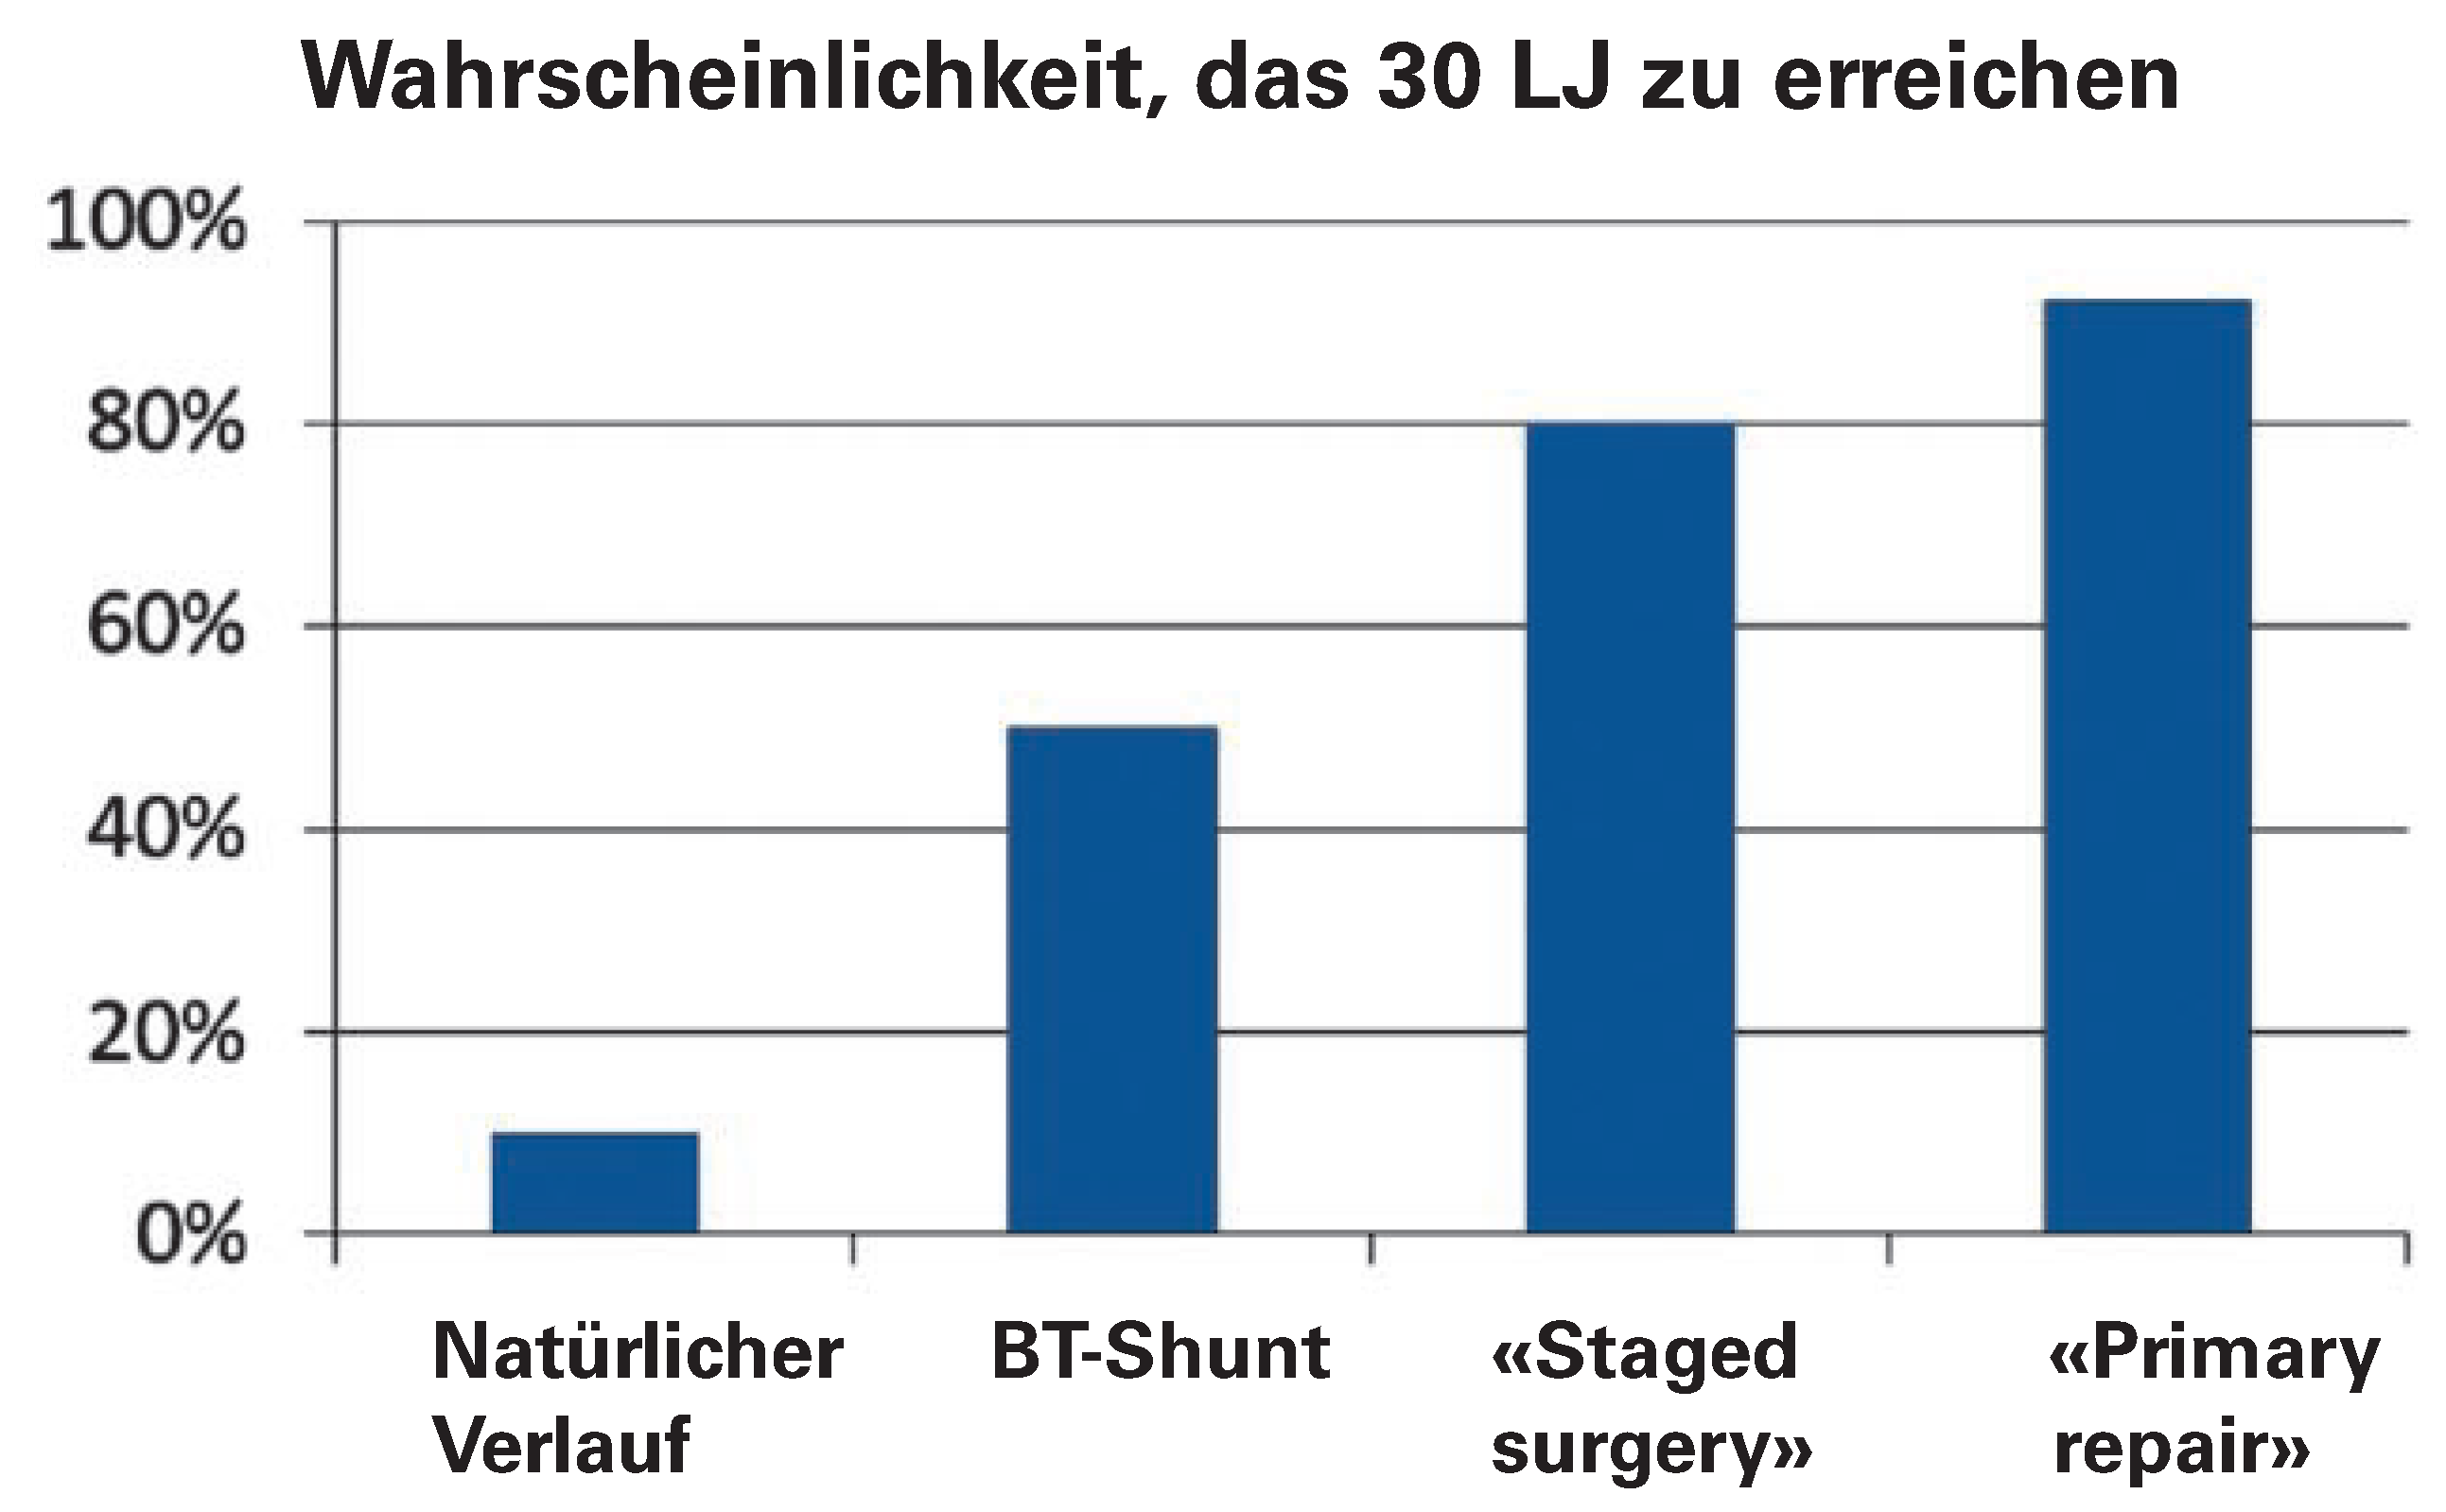

Insgesamt verbesserte die Einführung chirurgisch angelegter aorto-pulmonaler Verbindungen, insbesondere der Blalock-Taussig-Shunt, die Prognose der Fallot-Tetralogie deutlich. Die Wahrscheinlichkeit, das 30. Lebensjahr zu erreichen, stieg von 10% auf 50% [

Nach Einführung der Herz-Lungen-Maschine etablierte sich bis in die 1980er Jahre die Ära der «staged corrective surgery». Symptomatische Neugeborene und Kleinkinder mit Fallot-Tetralogie wurden initial mit einer aorto-pulmonalen Verbindung palliativ versorgt, und erst beim älteren Kind wurde der VSD verschlossen und die RVOT-Obstruktion behoben. Lillehei et al. publizierten 1986 die Ergebnisse der ersten 106 an der University of Minnesota operierten Fallot-Patienten [

15]. Die Überlebensraten nach erfolgreicher Korrektur betrugen 93%, 80% und 77% nach 10, 20 und 30 Jahren. Mitte der 1990er Jahre lag die 30-Jahre-Überlebensrate nach Fallot «Totalkorrektur» weiterhin unter der normalen Lebenserwartung (86% vs. 96%, p <0,01 in einer Arbeit aus der Mayo Klinik [

16]), konnte aber im Vergleich zur Überlebensrate mit lediglich aorto-pulmonale Anastomosen erneut um 25–30% verbessert werden.

17]. Der Pulmonal-Anulus war zum Korrekturzeitpunkt oft zu klein um das pulmonale Schlagvolumen ohne grösseren Gradienten passieren zu lassen. In der Annahme, dass eine radikale Korrektur mit tiefem Gradienten die beste Lösung sei, wurde der RV-Ausflussbahn durch ein Aufschneiden des Anulus und eine Erweiterung mittels Patch vergrössert. Dieser transanuläre Patch führt in aller Regel längerfristig zu einer schweren Pulmonalinsuffizienz. Abschliessende Zahlen bezüglich des 30-Jahres-Outcome nach Primärkorrektur fehlen noch, die Überlebenswahrscheinlichkeit dürfte mittlerweile >90% liegen [

18].

Abbildung 4 zusammengefasst.